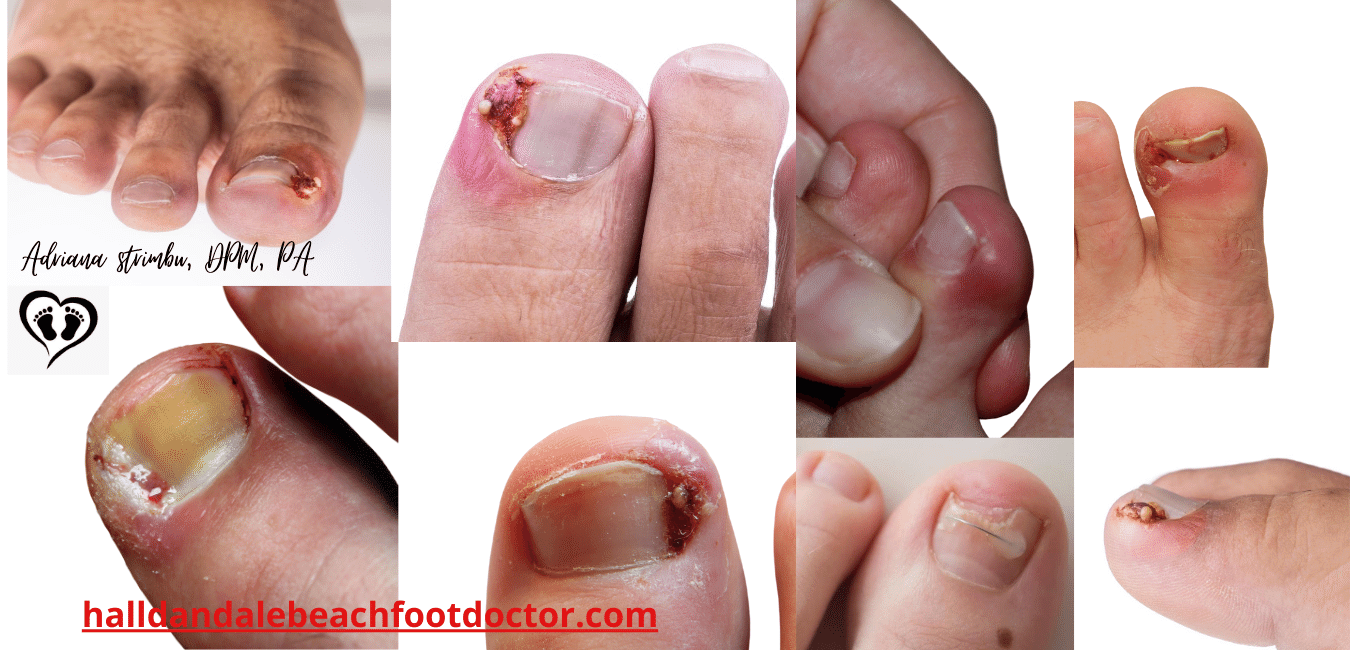

Ingrown Toenails Treatment Podiatrist Foot Doctor Hallandale

Ingrown Toenail Treatment Causes Prevention Foot Pain Explored

Ingrown Toenail Management in Singapore Straits Podiatry

Ingrown Toe Nail Removal And Treatment Doctor Chicago iL

Ingrown Toenail Treatment Brisbane The Ingrown Toenail Ctr

Ingrown Toenail Removal Treatments Ingrown Toenail Specialist